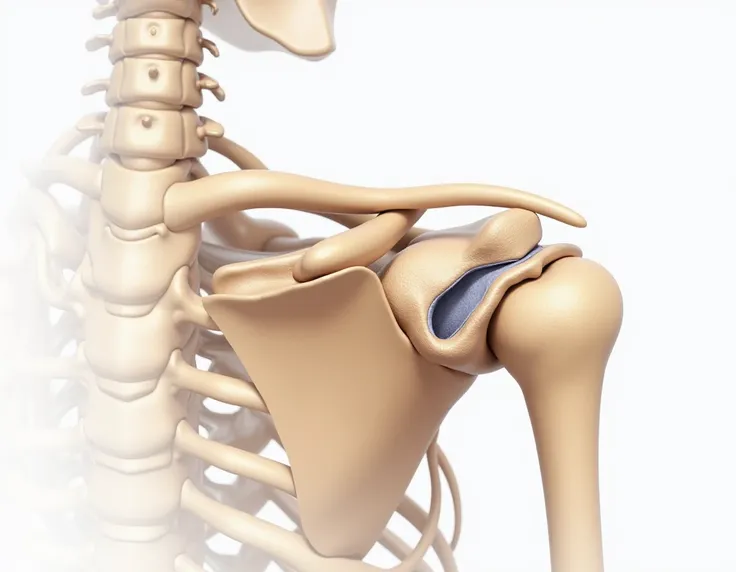

Close-up of human knee,There is a bone in the middle, knee, Knees, surreal bone structure, Protruding bones, Realphotos, orthographic view, Look across the shoulder, medical depiction, Osteoarticular joints, computer generated, hyper realisitc, sharp bone structure, joint, digital painted

Look across the shoulder

medical depiction

Osteoarticular joints

sharp bone structure